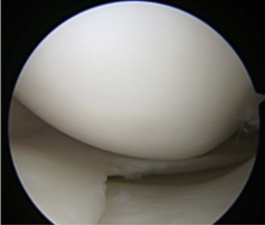

手術方法はともに関節鏡を用います。膝の前面に5mm程の傷を2箇所作り、関節鏡用の道具を用います。